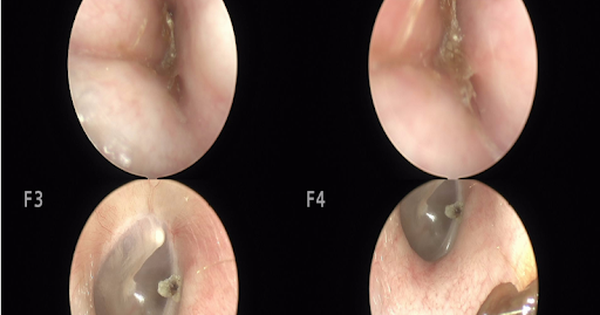

Ù tai, nghe kém, đi khám phát hiện lồi xương ống tai hiếm gặp